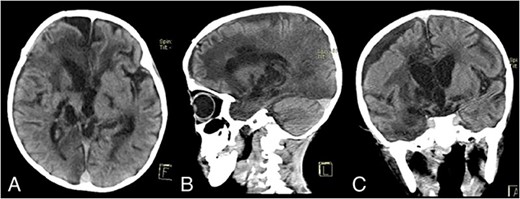

On Postoperative Day 2, the patient’s consciousness improved with GCS E2M5V2. The patient was given Ceftriaxone IV 2 × 750 mg, Metronidazole IV 3 × 110 mg, Paracetamol IV 4 × 150 mg, Captopril PO 3 × 3.125 mg, Furosemide PO 2 × 5 mg, and Digoxin 2 × 0.0625 mg. The patient was transferred to the nonintensive care ward on Postoperative Day 18. During hospitalization, the patient continued to have a fever, and he also contracted pneumonia. His sputum culture isolated Pseudomonas aeruginosa with resistance to Ampicillin, Cefepime, Ceftazidime, Meropenem, Ciprofloxacin, and Cotrimoxazole. Fortunately, the pathogen was still sensitive to Amikacin, and the patient was promptly given Amikacin IV 1 × 200 mg. The patient’s condition continued to improve, and after being 1 week free of fever, the patient was discharged after 50 days of hospitalization. His GCS on discharge was E3M5V2, with oxygen saturation of 70–80% without supplemental oxygen. A noncontrast head CT scan on discharge showed that the abscess had been completely removed (Fig. 2A–C).

Discharge noncontrast head CT scan showing that the abscess has been completely removed; (A) axial view; (B) sagittal view; (C) coronal view.